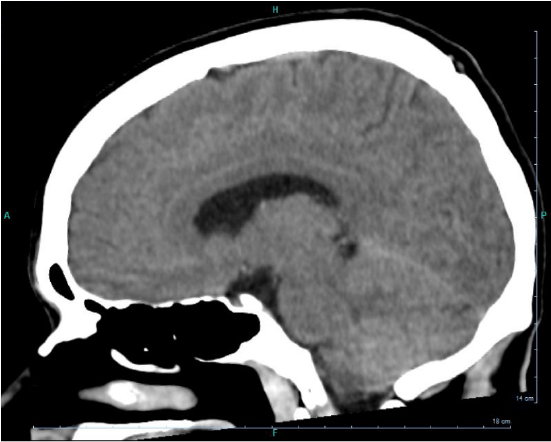

L’hypnose, comme tout phénomène psychique, dépend d’un processus neurologique avant tout. Voilà une vingtaine d’années que des chercheurs travaillent sur le sujet, prouvant au fil de leurs études que le cerveau hypnotisé mobilise des régions particulières.

Cerveau sous hypnose.png

Survolez les zones de couleur

Cerveau sous hypnose - Qu'est-ce que la transe hyp

Cliquez sur les mots en orange